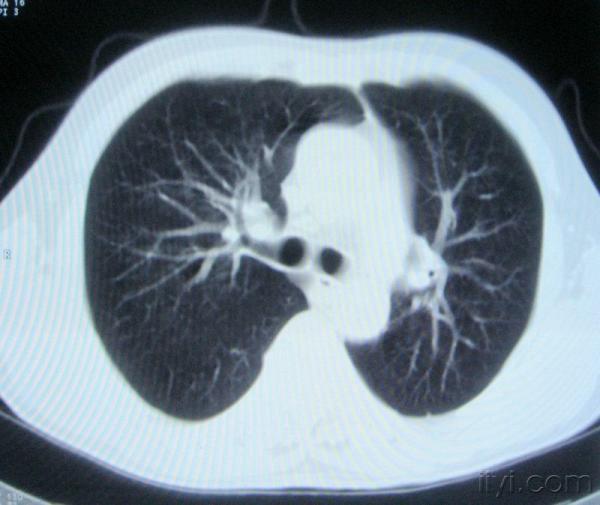

男。60岁,胸片示支气管炎治疗后复查CT。